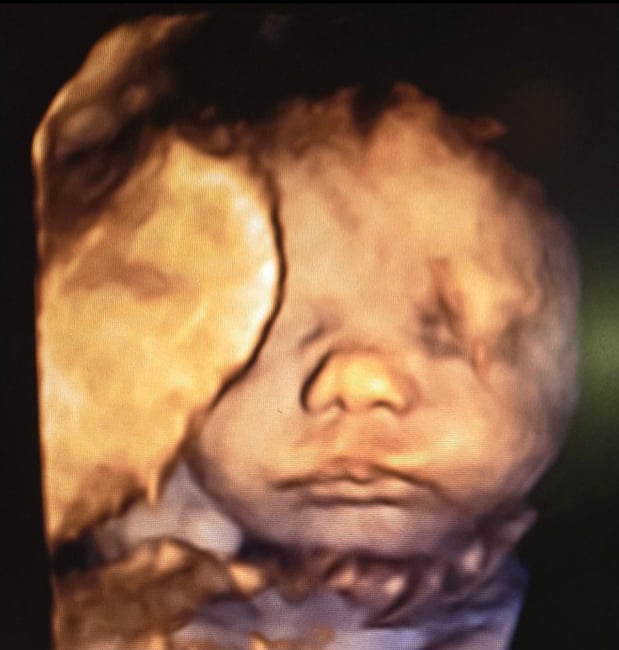

Tasha Crump, is registered by the American Registry of Diagnostic Medical Sonographers (ARDMS) and have over 18 years experience in medical diagnostic sonography specializing in Maternal Fetal Medicine. She is a highly proficient in the art of 3D 4D ultrasound. Tasha has practiced and trained in NYC's top ranked hospitals including Columbia Presbyterian. At Love at First Sight Imaging Studio you'll be in a very comfortable and calming atmosphere for you and your family to bond with your baby. We have state of the art equipment with HD Live to image unbelievably realistic views of your baby. You will fall in Love at First Sight.